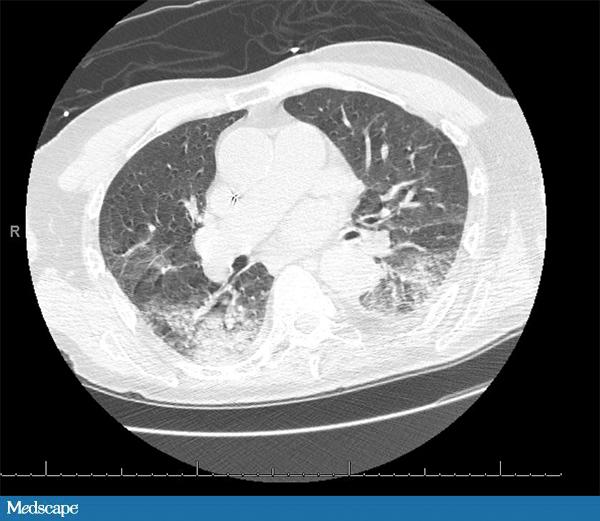

89 岁男性,有房颤、癫痫、痴呆病史。家属发现其昏迷并伴有右侧上下肢震颤,送至急诊科。患者的抗癫痫药于发病前一天吃完。体查示患者低烧(37.9°C),血压、心率、呼吸均正常。就诊时仍处于癫痫发作状态,遂予劳拉西泮解痉。患者白细胞 20,700/µL,中性粒细胞 77%。血红蛋白和血小板均正常。肌酐轻度升高(1.5 mg/dL)。心电图示房性节律,ST-T 波广泛性改变。肌钙蛋白 >40 mg/dL。CT 示“可能由吸入引起的双肺实变”。患者收入重症监护室。予头孢曲松控制肺炎,当晚换成舒巴坦。次日早晨,患者情况稳定,白细胞恢复正常。此时应如何进行下一步处理?

患者的临床症状和 CT 均提示轻度吸入性非细菌性肺炎(编者注:pneumonitis,这里应注意与 pneumonia 相区分,前者通常指吸入性的非感染性的炎症,比如胃液腐蚀性的;后者 pneumonia 常指感染性的肺炎,下文中同),这种情况可以发生于意识丧失期间。患者最主要的问题是心脏,白细胞升高很可能是心梗(肌钙蛋白阳性)造成。无发热且无明显的 CT 发现提示肺炎的可能性不大。另外,如果是常规感染性肺炎,白细胞不太可能这么快恢复正常。

吸入性非细菌性肺炎(pneumonitis)是吸入返流的胃内容物造成的,需进行气道管理。预防性使用抗生素不会对病情有利,反而会筛选出更加耐药的微生物。吸入性非细菌性肺炎是一种化学炎症反应,而通常所说的吸入性肺炎(pneumonia)是一个感染过程,二者常常混淆。通常所说的吸入性肺炎由吸入口咽部的分泌物导致,常见于神经性吞咽困难、胃和食管连接异常或上呼吸消化道解剖形态异常的患者。和吸入性非细菌性肺炎不同,通常说的吸入性肺炎需要抗生素治疗。我们可以通过发热、脓性分泌物和呼吸窘迫(呼吸急促、缺氧)与否对二者进行鉴别。